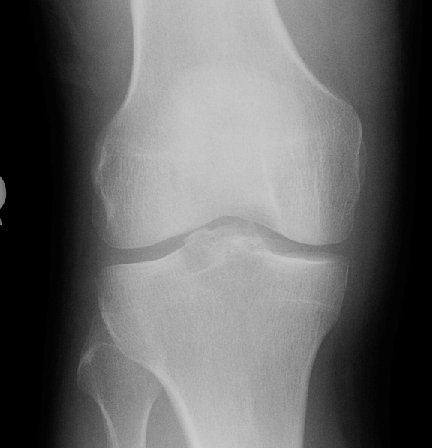

Return to Tibial Spine Fracture